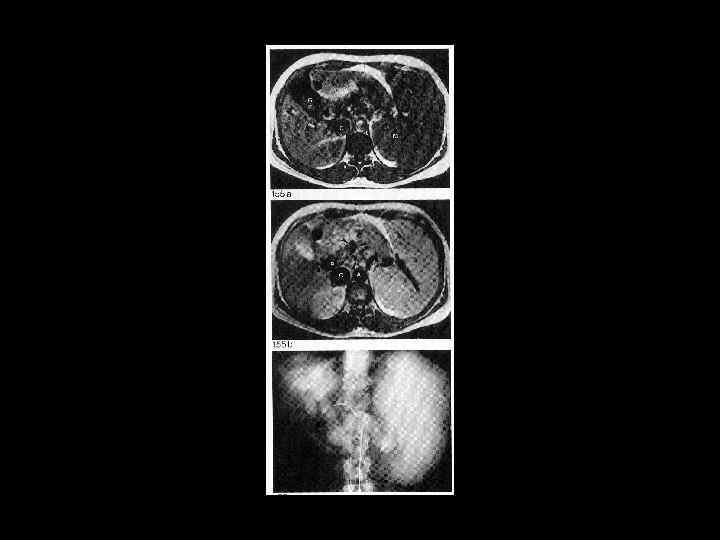

АКТУАЛЬНЫЕ ВОПРОСЫ РЕНТГЕНОЛОГИИ ЛУЧЕВАЯ ДИАГНОСТИКА ЗАБОЛЕВАНИЙ СЕЛЕЗЕНКИ Кисты и абсцессы селезенки

АКТУАЛЬНЫЕ ВОПРОСЫ РЕНТГЕНОЛОГИИ ЛУЧЕВАЯ ДИАГНОСТИКА ЗАБОЛЕВАНИЙ СЕЛЕЗЕНКИ Травма и инфаркт селезенки